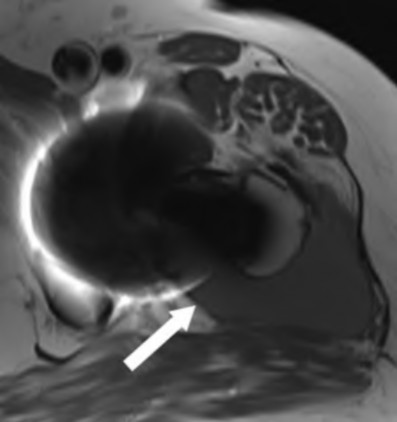

A 75-year-old man underwent total hip arthroplasty 10 years ago. He now reports mild groin pain which has been increasing lately. What is the most likely explanation for the finding in Figure A indicated with the arrows?

Osteolysis of the pelvis is a common complication associated with total hip arthroplasty. Osteolysis affects sockets with and without cement, and has been attributed to the biologic reaction to wear debris. With well-fixed cementless sockets, an expansile pattern of osteolysis is usually seen.

The radiographic appearance has a radiolucent area that starts at the implant-bone interface and expands into the cancellous bone away from the implant.

This pattern of osteolysis can be explained with the concept of effective joint space. This concept states that joint fluid and wear particles will flow according to pressure gradients and follow the path of least resistance.

The Level 5 review article by Chiang discusses osteolysis in further depth.